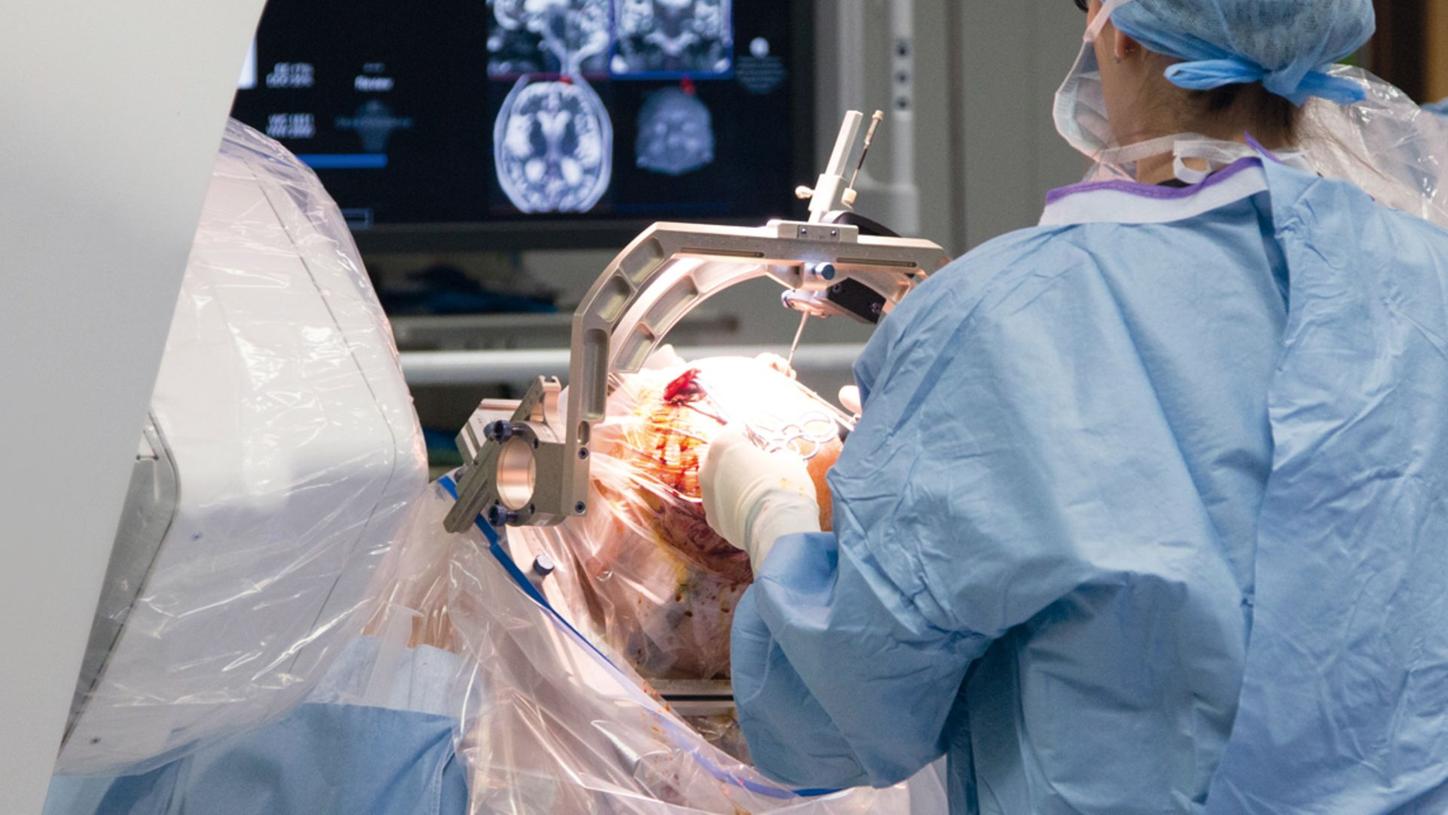

न्युरो इन्टरभेन्सनका अब्बल युवा डाक्टर

सोमबार, असोज १८, २०७८